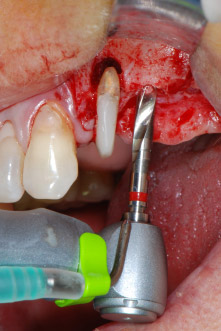

moteur d'implantologie

Fig. 8 : Préparation par rotation du lit implantaire avant le plancher du sinus maxillaire en position 25, effectuée à l'aide d'un nouveau moteur d'implantologie.

Les lits implantaires ont été préparés sur les sites 25 et 26 à l'aide d'instruments rotatifs, utilisés dans un contre-angle avec un rapport de transmission 20:1 avec un nouveau moteur d'implantologie puissant (Implantmed, W&H) (Fig. 8).

La préparation finale près du sinus a encore une fois été réalisée à l'aide d'un instrument piézoélectrique (Piezomed, insert S2).